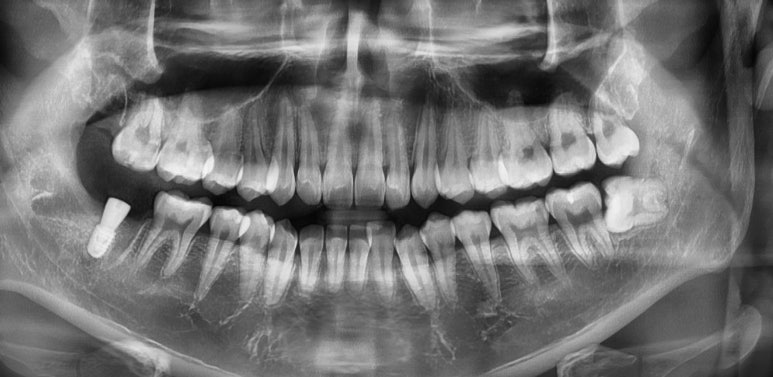

임플란트 픽스처 식립 후

20대 남성

2023-07-25

다행히 발치 당일에 임플란트 식립이 가능하다고 판단되어 오른쪽 위아래 사랑니와 함께

#47 치아를 발치하고 바로 임플란트를 식립할 수 있었습니다.

3개월 후 치아 역할을 해줄 보철물까지 올리기로 했는데요.

아마 올해 10월 쯤이면 환자분도 새로운 치아를 갖게 되실 것 같습니다 ^^